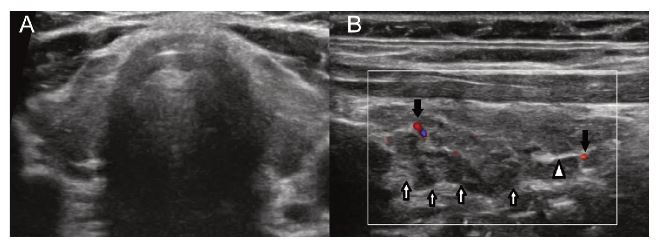

- Estudios de imagen, si se sospecha patología estructural